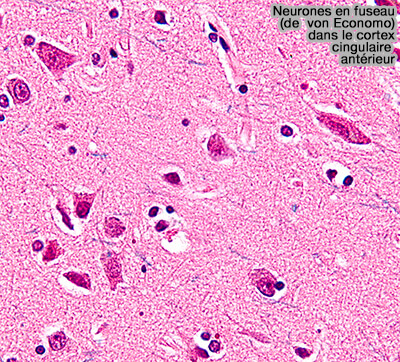

Neurones de von Economo (VEN) ou neurones en fuseau

Les neurones de von Economo (VEN) ou neurones en fuseau sont un type particulier de neurones trouvés dans la couche V.

Ces neurones ont été découverts et décrits pour la première fois en 1925 par le psychiatre et neurologue autrichien Constantin von Economo (1876-1931).

1. Les VEN sont bipolaires et caractérisés par, par exemple du cortex fronto-insulaire  :

• leur soma ou corps cellulaire de grande taille en fuseau, d'où leur nom,

• un axone apical (ou dendrite apicale) unique s'étendant vers la surface corticale,

• une unique dendrite basale tournée vers la substance blanche.

Les dendrites des VEN adjacentes s'alignent parallèlement les unes aux autres et partagent ainsi une orientation spatiale commune perpendiculaire à la surface corticale (The von Economo neurons in frontoinsular and anterior cingulate cortex in great apes and human 2010).

Neurones en fuseau (de von Economo)

(Figure : vetopsy.fr d'après Nephron)